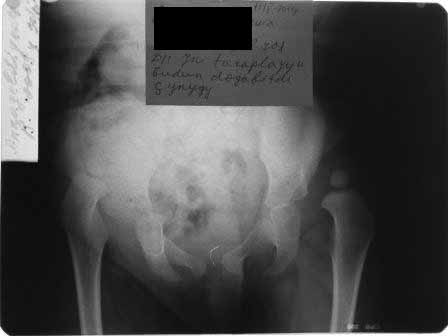

раскажу о технике закрытого вправления у детей, особенно при высоких вывихах. до 3 -х лет мы применяем лейкопластырное, крайне редко скелетное вытяжение, наложив лейкопластыри на конечности, ноги ребенка  вертикально подвешивается, дале постепенно в течении 14 дней ноги разводятся в стороны при этом, поверхность кровати поднимается вверх(разведение ног быстрее до 3-4 дней), масса груза до 25 процентов тела, но крайне важно, что бы при подвешивании ягодицы (попа ребенка) были немного на весу. через 2 недели при не высоких вывихах без наркоза по лоренцу ручное вправление, при высоких вывихах под наркозом и часто сочетается подкожной  миотомией аддукторов бедра, ручное вправление. вот пример девочка 2 лет